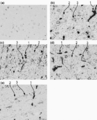

- the drawing substitute photograph which shows the result of the immunohistochemical staining for the humanized anti-hTfR antibody of the cerebral cortex of the cynomolgus monkey after single intravenous administration.

- A administer Herceptin,

- b administer humanized anti-hTfR antibody # 3,

- c administer humanized anti-hTfR antibody # 3-2

- d administer humanized anti-hTfR antibody # 3

- E Administration of humanized anti-hTfR antibody No. 3-2 (IgG4).

- the bar on the lower right of each photograph is a gauge representing 20 ⁇ m.